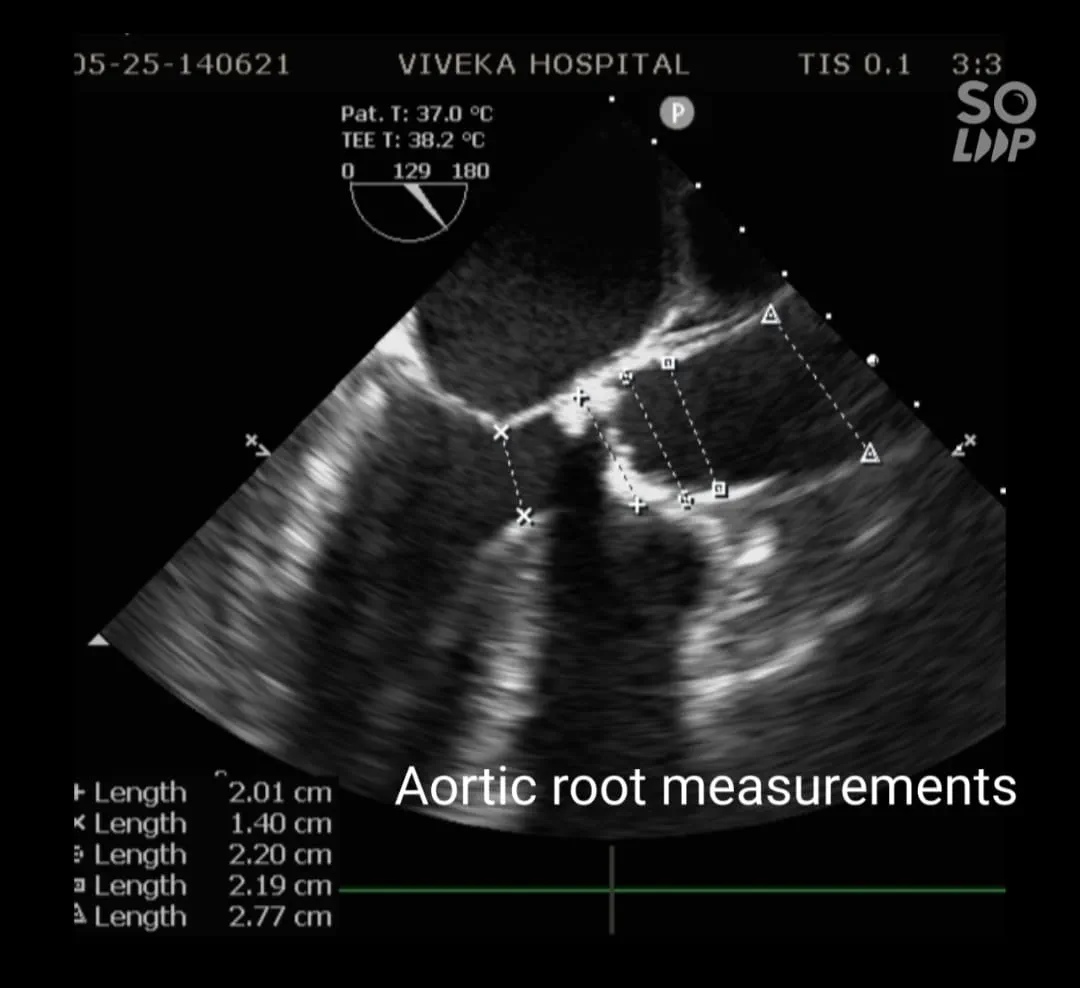

Transoesophageal echocardiography: Findings of Transthoracic ECHO confirmed. Aortic annulus : 20.1mm

Gradient : 128/50 mm of Hg. Mild Aortic regurgitation. Severe Concentric Left ventricular hypertrophy. Calcific Aortic Valve with area 0.349 cm2.